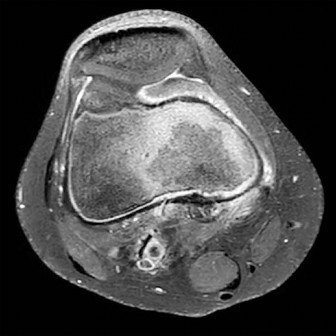

An 8-year-old Japanese girl presents with a painless, palpable 'clunk' on the lateral side of her left knee during terminal extension. MRI confirms a discoid lateral meniscus. Which specific variant of a discoid meniscus is characterized by an absent posterior meniscotibial attachment, leading to hypermobility and snapping?